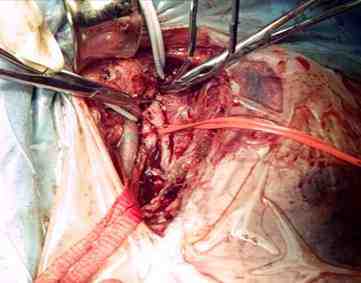

Cirugía realizada: trombectomía venosa iliofemoral izquierda

Hallazgos: trombosis venosa iliofemoral con disminución del flujo arterial distal